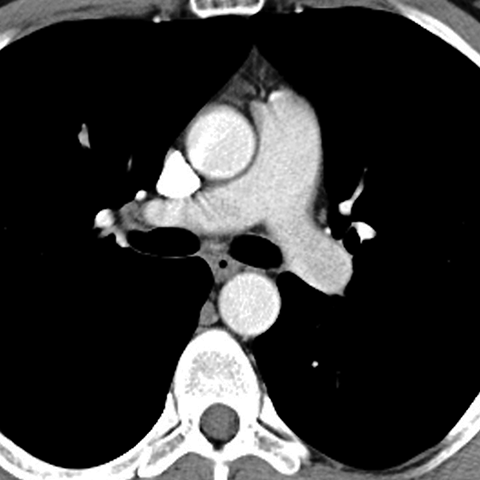

Normal Mediastinum (Axial CT) [4 of 5]